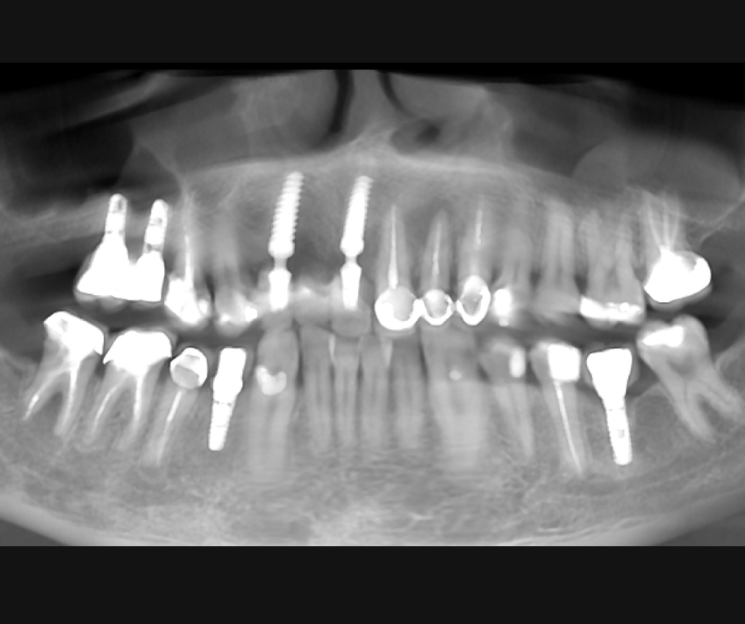

Extracción de piezas 21, 22 y 23 con infección activa

Paciente con infecciones de origen dental que comprometían severamente el hueso alveolar en la zona anterior superior. Se realizó la extracción de los dientes 21, 22 y 23, y se optó por una rehabilitación inmediata mediante implantes córticobasales.

- 1 implante córticobasal compresivo

- 2 implantes córticobasales rectos y finos

Esta combinación permitió anclar los implantes en hueso cortical, que mantiene su estabilidad incluso en presencia de procesos infecciosos en el hueso alveolar. El resultado: rehabilitación funcional y estética el mismo día de la cirugía.

La rehabilitación postextracción de los dientes 21, 22 y 23 con implantes córticobasales no es un caso aislado. Es un ejemplo claro de cómo la odontología moderna puede resolver situaciones complejas de forma inmediata, estética y funcional.